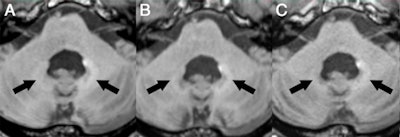

In the current retrospective study, Radbruch and colleagues narrowed their focus to possible evidence of signal intensity on unenhanced T1-weighted MR images in the dentate nucleus of patients who received an average of 23 injections of macrocyclic GBCAs.

Signal intensity ratio differences were calculated based on dentate nucleus-to-pons and dentate nucleus-to-middle cerebellar peduncle (MCP) values by subtracting the signal intensity ratio of the first MRI scan from the signal intensity ratio at the last MRI exam. The mean interval between the first and last MRI scans was 273 weeks.

The researchers found no significant T1 signal increase in the dentate nucleus in any of the patients after a mean 23 serial injections of the macrocyclic GBCAs. The findings were reinforced by the dentate nucleus-to-pons ratio of -0.0032 ± 0.0154 (p = 0.248) and the dentate nucleus-to-MCP ratio of -0.0011 ± 0.0093 (p = 0.521).